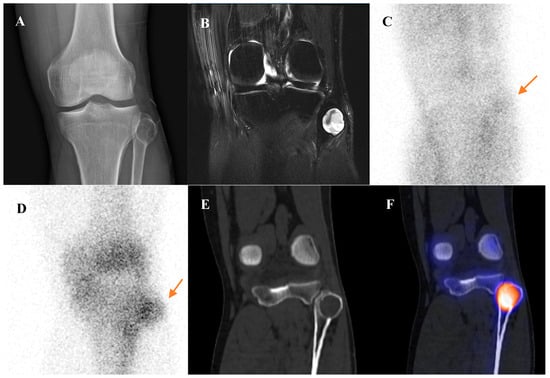

Figure 3 illustrates the spectrum of cartilaginous tumors, from low-grade ACT with mild metabolic activity to high-grade chondrosarcoma with aggressive infiltration and intense uptake, emphasizing the importance of integrating multimodal imaging with histopathology for accurate diagnosis and grading.

Figure 3.

(A–E) A 54-year-old male with atypical cartilaginous tumor (ACT) of the left distal femur. (A) Bone scintigraphy shows increased uptake in the distal metaphysis. (B) Radiograph demonstrates stippled calcifications suggestive of a chondroid tumor. (C) T2-weighted fat-suppressed magnetic resonance imaging (MRI) shows a lobulated intramedullary lesion with heterogeneous signal and equivocal cortical erosion. (D) Bone single-photon emission tomography (SPECT)/computed tomography (CT) demonstrates focal uptake in the distal femur, corresponding to a calcified chondroid mass. (E) [18F]FDG positron emission tomography (PET)/CT shows mild, elongated uptake (SUVmax 2.96) in the lesion with characteristic rings-and-arcs calcification on CT. Surgical excision confirmed ACT. (F–J) A 49-year-old female with high-grade chondrosarcoma of the left acetabulum (F) Bone scintigraphy shows intense uptake. (G) Radiograph demonstrates a geographic radiolucent lesion. (H) T1-weighted fat-suppressed MRI reveals an infiltrative lesion with extraosseous and intra-articular extension, heterogeneous enhancement. (I) SPECT/CT reveals increased uptake in the acetabular region, corresponding to the infiltrative lesion with extraosseous extension. (J) [18F]FDG PET/CT demonstrates intense localized uptake in the left acetabulum with extension into the obturator internus muscle, especially pronounced at the site of extraosseous spread (SUVmax 8.4). Initial biopsy suggested grade I chondrosarcoma; however, wide excision confirmed dedifferentiated chondrosarcoma.